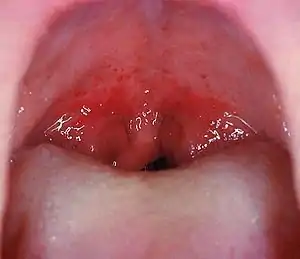

Angines

Ce sont de loin les plus fréquentes conséquences des streptocoques hémolytiques. Environ 45 % des angines rouges et pultacées sont dues à ces streptocoques (l'étiologie des autres angines est virale dans 45 % des cas, celle des 10 % restants est due à des germes divers: diphtérie, staphylocoques, haemophilus, association fuso-spirillaire de Vincent, monilias et mycoplasmas).